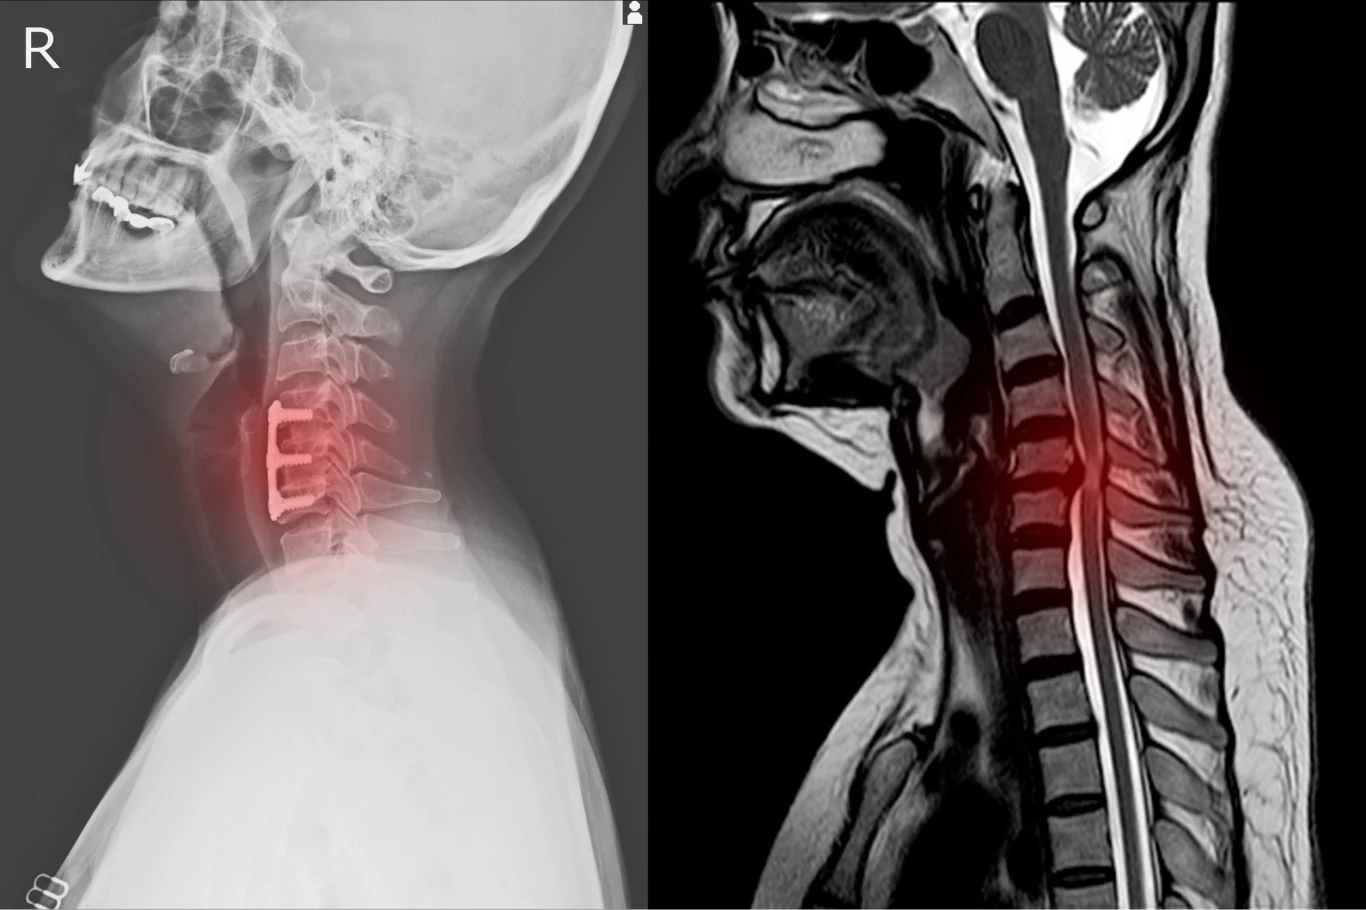

- Zrozumienie, w jaki sposób rdzeń kręgowy kontroluje nasze ciało, jest niezbędne do poprawy leczenia zaburzeń ruchowych spowodowanych urazem lub chorobą układu nerwowego. Zbadaliśmy funkcję rdzenia kręgowego u ryb danio, ponieważ one i ssaki mają wiele wspólnych neuronów rdzeniowych. Te słodkowodne ryby są szeroko stosowanym organizmem modelowym w badaniach biomedycznych - powiedział prof. Tuan Bui, jeden z autorów przeprowadzonych badań.Rdzeń kręgowy to długa, cienka, rurkowata struktura, która rozciąga się od pnia mózgu do dolnej części kręgosłupa. Skrywa się w nim kilka populacji neuronów, które pomagają kontrolować wszystkie mięśnie ciała i koordynować ruchy. Naukowcy nie rozumieją jeszcze roli poszczególnych neuronów i tego, jak one się ze sobą komunikują, ale są coraz bliżej poznania prawdy.- We wczesnym okresie rozwoju, w rdzeniu kręgowym powstają nowe neurony i nowe połączenia między neuronami rdzeniowymi. U młodych zwierząt, w tym u niemowląt, powstawanie nowych neuronów i tworzenie połączeń neuronalnych zbiega się w czasie ze zdolnością do wykonywania nowych, bardziej zręcznych manewrów w miarę wzrostu i dojrzewania organizmu. Jednym z podejść do zrozumienia, w jaki sposób rdzeń kręgowy kontroluje nasze ciało, jest zbadanie, w jaki sposób nowe neurony i połączenia są odpowiedzialne za zdobywanie nowych ruchów - dodał prof. Tuan Bui.Naukowcom udało się stworzyć modele rdzenia kręgowego na różnych etapach rozwoju. Przeprowadzone symulacje wykazały, że nabycie umiejętności pływackich u ryb danio zbiegło się w czasie z pojawieniem się specyficznych neuronów. Umożliwiły one rdzeniowi kręgowemu kontrolowanie tempa i czasu trwania nowych ruchów.- Zidentyfikowaliśmy również wzorce aktywności neuronalnej, które powtarzają się w różnych ruchach. Na przykład, aby wykonać uderzenia ogona, które są naprzemienne po lewej i prawej stronie, neurony po jednej stronie rdzenia kręgowego pobudzają neurony po drugiej stronie. Jednakże ta aktywacja w całym ciele jest precyzyjnie rozłożona w czasie, aby zapewnić każdej stronie wystarczającą ilość czasu na wygenerowanie uderzenia ogona. Te wzorce mogą być obecne w sposobie, w jaki ludzie wykonują czynności lokomotoryczne, takie jak chodzenie i pływanie - podsumował prof. Bui.Przeprowadzone badania pozwolą zidentyfikować nowe funkcje różnych neuronów w rdzeniu kręgowym i ich związek z przeprowadzanymi ruchami. To z kolei może być przydatne w tworzeniu nowych terapii przywracających ruchy osobom sparaliżowanym.